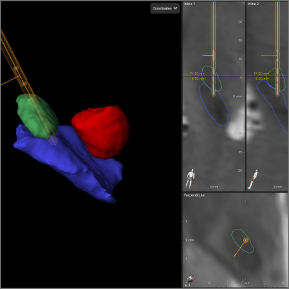

See how Image Guided DBS works:

Images are collected during your DBS procedure.

Collected images are evaluated to see the exact location of your leads.

The images are loaded into the programming software and therapy is programmed precisely – based on the location of your leads.